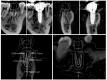

The purpose of this review is to examine various assessment methods in order to compare the accuracy between the virtually planned and clinically achieved implant positions. In this review, comparison methods using pre- and post-operative computed topography (CT) data and digital impressions for definitive prosthesis will be described. The method for the displacement and strain for quantification of the error will also be explored. The difference between the planned and the actual implant placement position in guided implant surgery is expressed as an error. Assessing the accuracy of implant-guided surgery can play an important role as positive feedback in order to reduce errors. All of the assessment methods have their own inevitable errors and require careful interpretation in evaluation.